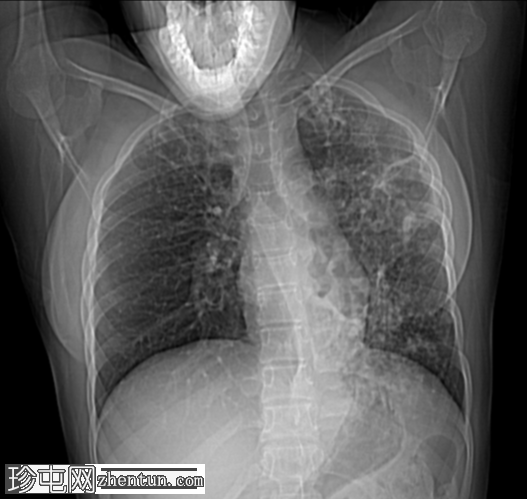

双侧肺部可见气腔实变和空洞,肺壁厚(左上叶和左下叶最大),伴支气管周围增厚,多发树芽征和结节征。

Gene Xpert MTB-RIF 检测,痰液结核杆菌阳性

痰涂片抗酸杆菌(3 份),Z.N 染色阳性